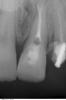

SergioS Опубликовано 27 апреля, 2013 Поделиться Опубликовано 27 апреля, 2013 Уважаемые коллеги, подскажите как бы кто поступил в данной ситуации:21 наружняя резорбция, в канале цемент, при попытке ревизии выскочили в резорбцию, инструмент заклинил и остался. В канале Vitapex, последние 2 мм не пройдены.У нас варианта 2:1.Пломбировка альфа-гуттой, хирургическим путем извлечь инструмент, MTA, остеопластический материал и под наблюдение.2..Пломбировка альфа-гуттой, резекция,MTA, остеопластический материал и под наблюдение.Снимки. Ссылка на комментарий

ger_berra Опубликовано 27 апреля, 2013 Поделиться Опубликовано 27 апреля, 2013 Мой вариант.Ортоградная ревизия через кальций,паковка,отрезать корень до уровня резорбции с деконтаминацией поверхности,не дожидаясь динамики.Потому как ортоградно остановить внешнюю резорбцию,на сколько мне известно,невозможно.Реставрация безметалл.Благо,что условия позволяют не пихать в корень вкв. 1 Ссылка на комментарий

Снежана Опубликовано 27 апреля, 2013 Поделиться Опубликовано 27 апреля, 2013 я бы сделала так: канал ортоградно обтурировать мта, потом просто хирургически удалить фрагмент, срезать непройденные мм апекса до мта, резорбированную поверхность корня зачистить уз. зачем вам делать мта ретроградно? это гораздо сложнее. Ссылка на комментарий

SergioS Опубликовано 28 апреля, 2013 Автор Поделиться Опубликовано 28 апреля, 2013 (изменено) Я стал склоняться к варианту без резекции. Просто ревизия и извлечение инструмента с деконтаминацией и ретроградкой легкой. Изменено 28 апреля, 2013 пользователем SergioS Ссылка на комментарий